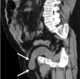

Bladder hernia

An inguinal hernia is a protrusion of abdominal-cavity contents through the inguinal canal. Symptoms are present in about 66% of affected people. [Source: Wikipedia ]